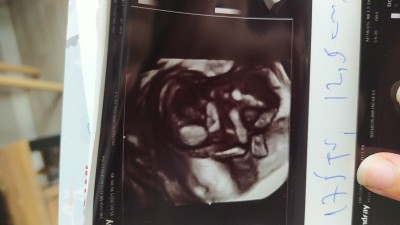

16.haftadayiz doktorumuz kız bebek diyo ama sonradan yanilabilrim diyor.

Gebelik haftası 16.hafta